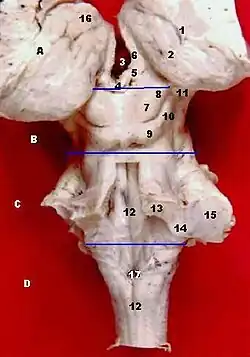

1. Taenia choroidea (lateral: Lamina affixa, Stria terminalis) 2. Tálamo, Pulvinar thalami 3. III ventrículo 4. Tallo de la epífisis 5. Habénula 6. Stria medullaris 7. colículo superior 8. Brazo del colículo superior 9. colículo inferior 10. Brazo del colículo inferior 11. Núcleo geniculado medial 12. Sulcus medianus 13. pedúnculo cerebeloso superior 14. pedúnculo cerebeloso inferior 15. pedúnculos cerebelosos medios 16. Tubérculo anterior del tálamo 17. Obex cerebral, Área postrema | ||